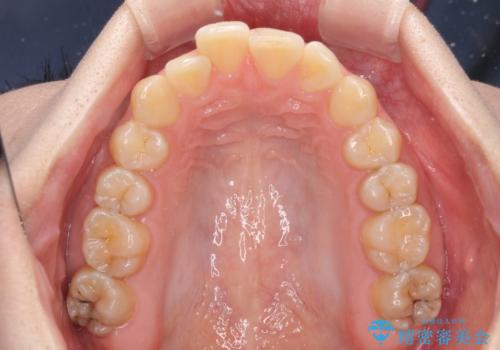

前歯のデコボコをインビザライン矯正で綺麗に改善

- 上下前歯のデコボコを気にして来院された患者様です。

全体的に叢生は軽度であったため、インビザラインにて矯正治療を行うこととしました。

舌の突出癖改善がうまくいかず、途中で舌小帯の切除を行いました。

気になる段差を納得いくまで改善させたため、治療期間は長くなりましたが、綺麗な仕上がりとなりました。